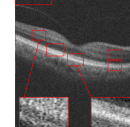

The proposed algorithm has been also tested for the super-resolution of the two other datasets. For dataset2, the middle slices of several 3D image have been selected for test and averaged with 2 previous and 2 next slices. The weights ’s set equal to for each B-scan. For the proposed approach, the patch sizes were set equal to 5 and 7 or (5 and 10) with window size equal to [2,2]. For MDT the window size was set to [2,2]. The results for the super-resolution of artificially missed B-scans of dataset2 with missing ratio have been illustrated in Fig. 6. Since this dataset does not contain reference images, PSNR and SSIM could not be reported. Hence, only visual comparison and the resulting CNR’s, with the following definition, have been reported for each algorithm:

where and are the mean and standard deviation of the foreground respectively and and are the mean and standard deviation of the background region, respectively. Averaged CNR’s for 5 Regions Of Interest (ROI) in each image (relative to an ROI selected in the background region of the image) have been computed. Note that ROI’s have been shown with red boxes in each image of Fig. 6. As the results show, the proposed algorithm results in a better output and higher CNR comparing to the other algorithms.